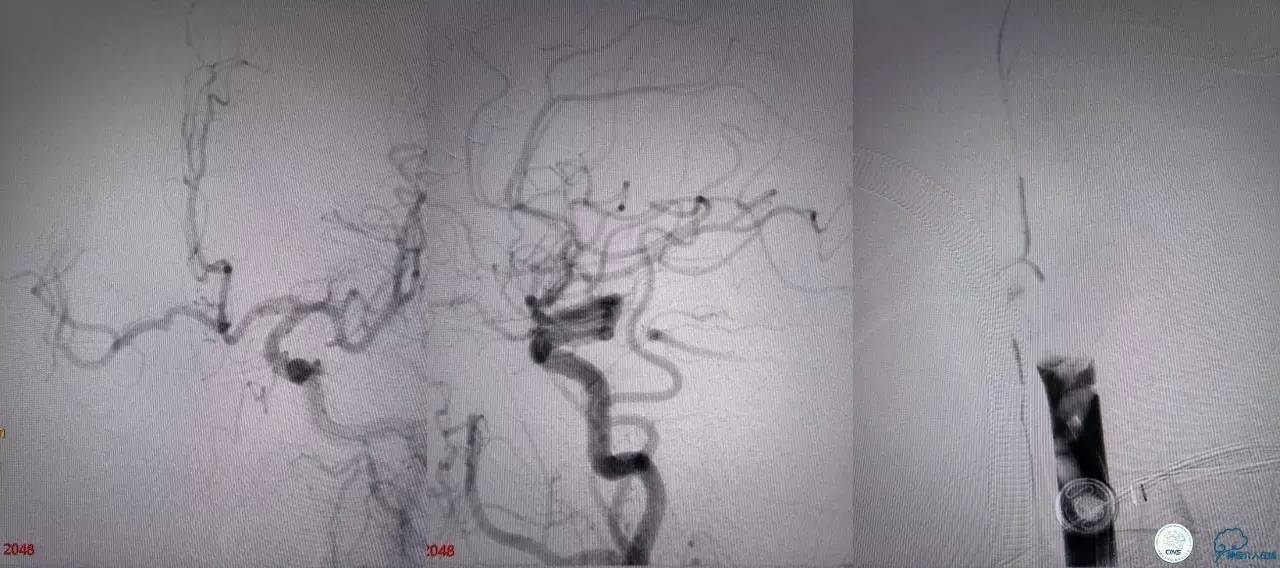

基底动脉顶端仍有大量血栓,双侧大脑后动脉未见显影,双侧小脑上动脉再通。再次取栓?还是动脉溶栓?

决定导管内给予替罗非班6ml,复查造影BA顶端仍闭塞,第二次取栓。

第二次取栓后可见基底动脉顶端仍有大量血栓,右侧大脑后动脉开通,但左侧大脑后未见显影且左侧小脑上动脉闭塞!

第三次取栓,支架放入左侧大脑后取栓。

第三次取栓后,左侧大脑后动脉开通,但是栓子再次栓塞右侧大脑后动脉,血栓在基地动脉顶端来回左右摆动,下一次,怎办?血栓负荷太多,可以使用solumbar技术,可以没有颅内导管,没办法,换用更大的支架6-20mm,但费用增加不少,与家属沟通后同意使用,第四次取栓:

血栓负荷还是很大,左侧大脑后再通,但右侧大脑后又闭塞,只能第五次取栓,支架放到右侧大脑后动脉更远。